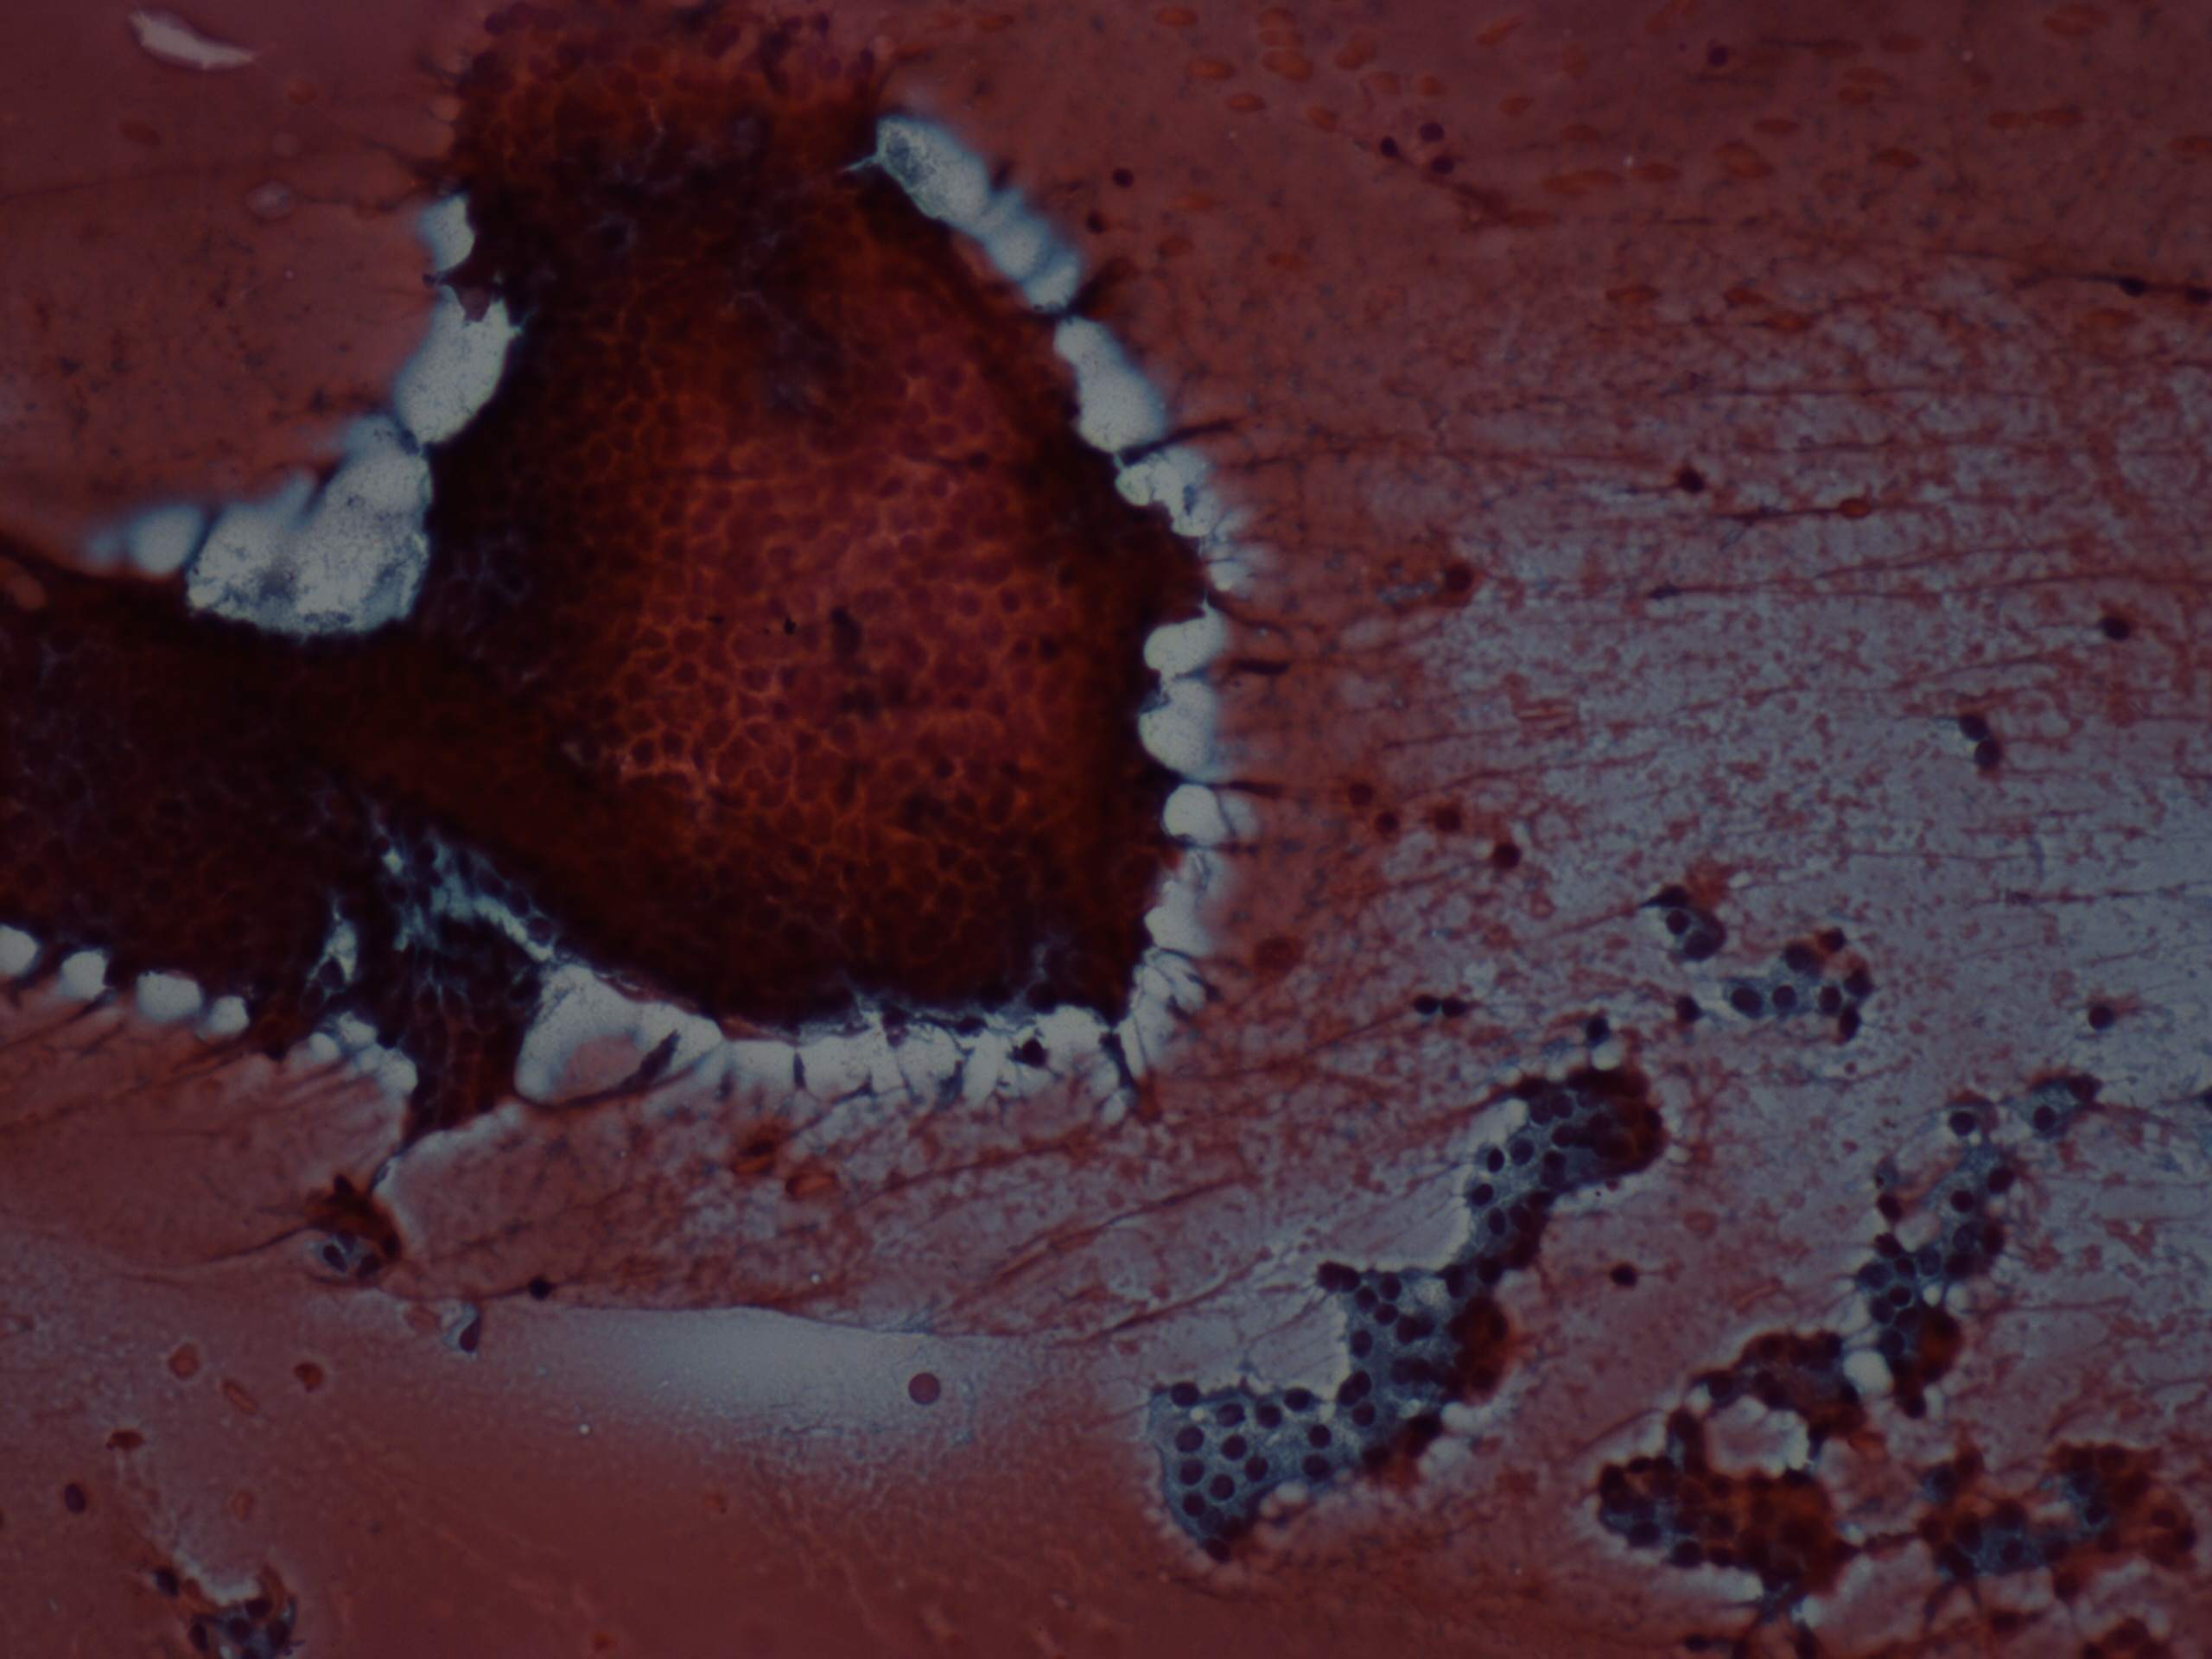

Benign nodular hyperplasia - Case 46. (cytologic picture 2)

Pap-smear, 200x. Note the vacuolization on the periphery of the papillary cluster.